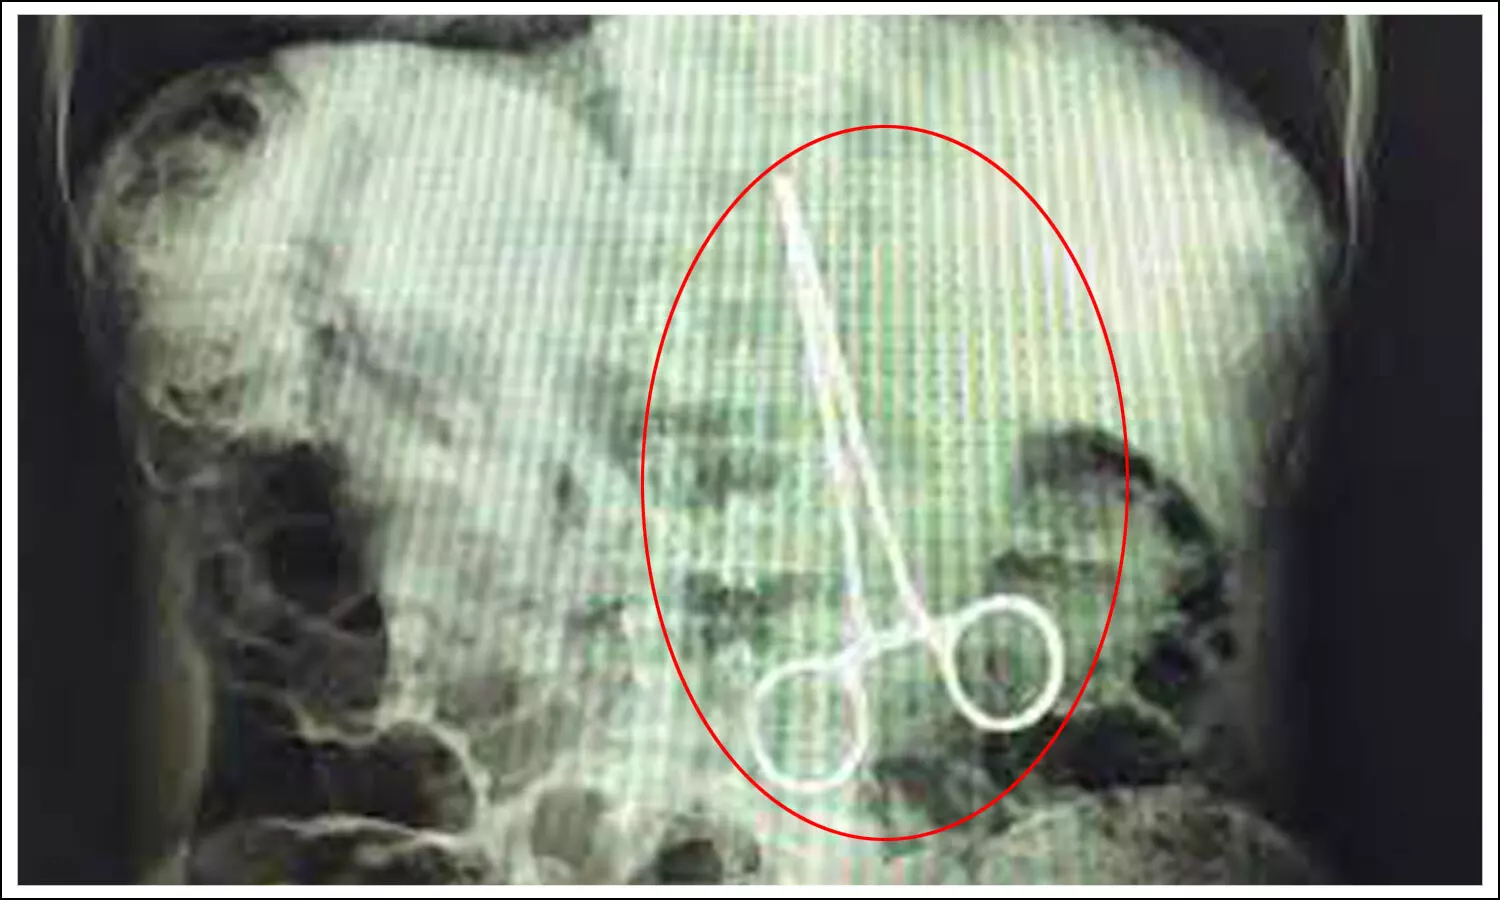

ఆగస్టు 10వ తేదిన ఏలూరు నుంచి స్వప్న అనే మహిళను విజయవాడలోని ప్రభుత్వ ఆసుపత్రికి తీసుకొచ్చారని తెలిపారు. అయితే సర్జికల్ ఫోర్సెప్ (కత్తెర)ను ఆమె కడుపులోనే వదిలేశాని పేర్కొన్నారు. ఆ కత్తెర పొడవు రెండు ఇంచుల వరకు ఉందని వైద్యులు చెబుతున్నారు. కడుపులో వదిలేసిన కత్తెర పేగకి అతుక్కుపోవడంతో ఆమెకు కడుపు నొప్పి తీవ్రమైంది. దీంతో కత్తెర అతుక్కుపోయిన పేగు కుళ్లిపోయిందని అన్నారు. , ప్రస్తుతం ఆ కుళ్లిపోయిన పేగును తీసేసి చికిత్స నిర్వహిస్తున్నామని వైద్యులు తెలిపారు. దీంతో మహిళ ఆరోగ్య పరిస్థితి ప్రస్తుతం నిలకడగా ఉందని విజయవాడ ప్రభుత్వ ఆసుపత్రి వైద్యులు ప్రభాకర్, సర్జరీ విభాగాధిపతి అప్పారావులు వెల్లడించారు.

వివరాల్లోకి వెళితే..పెదపాడు మండలం ఎస్.కొత్తపల్లి అనే గ్రామానికి చెందిన స్వప్న ప్రసవం కోసం ఏప్రిల్ 19వ తేదిన బోధనాసుపత్రిలో చేరింది. అయితే గర్భిణీతో ఉన్న ఆమెకు ఆపరేషన్ చేసి బిడ్డను బయటకు తీశారు. అయితే మహిళకు తీవ్ర కడుపు నొప్పి రావడంతో ఆమె పరిస్థితి ఆందోళకరంగా మారిందని వైద్యులు తెలిపారు. అయితే వైద్యులు ఆమెకు ఆపరేషన్ చేసిన తర్వాత డిశ్చార్జి చేశారు. ఇంటికి వెళ్లిపోయిన స్వప్నకు తరచుగా కడుపు నొప్పి వచ్చేది. ఇలా నొప్పులు వచ్చినప్పుడు సాధారణంగా వచ్చే నొప్పులు ఏమో అనుకుని మందులు వాడేది. అయితే ఆగస్టు 8వ తేదిన స్వప్నకు విపరీతంగా కడుపు నొప్పి వచ్చింది. దీంతో తిరిగి ఏలూరులోని బోధనాసుపత్రికే వెళ్లింది. కానీ అక్కడ వైద్యులు ఆమెకు పరీక్షలు చేసిన తర్వాత విజయవాడలోని ఆసుపత్రికి సిఫార్సు చేశారు. దీంతో అక్కడ ఆమెను పరీక్షించగా అసలు విషయం బయటకు వచ్చింది. స్వప్న కడుపులో కత్తెర ఉన్నట్లు ఎక్స్రే ద్వారా బయటపడింది.